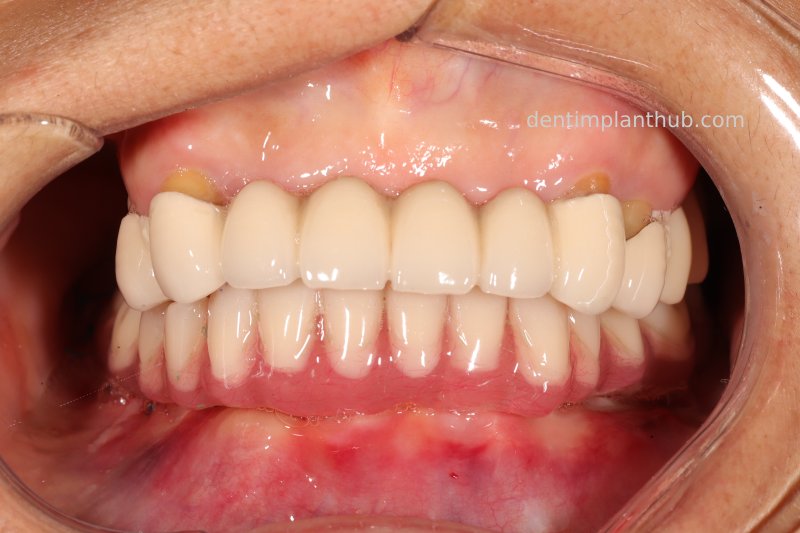

Temporary crown photograph of the upper jaw on 7 June 24

Photo of temporary crown worn into the mouth on the day of surgery, 7 June '24